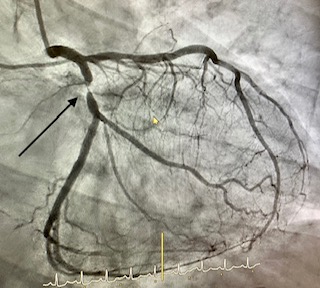

Angioplastia con stent

La angioplastia coronaria transluminal percutánea con implantación de stent ha sido capaz, en las salas de RX de los laboratorios de Hemodinámica y Cardiología Intervencionista, de combatir eficazmente a la enfermedad que más mortalidad causa en las sociedades modernas: la enfermedad coronaria.